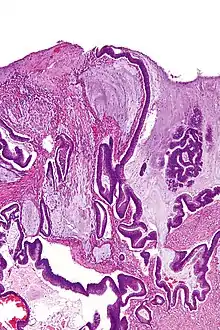

| Micrograph of a mucinous adenocarcinoma of the colon. H&E stain. | |